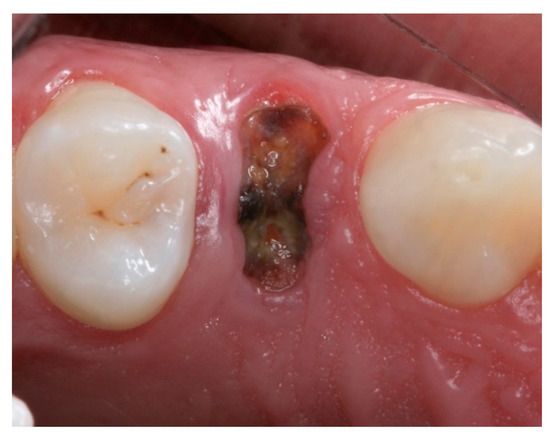

2.4. Groups

2.5. Post-Surgical Procedures